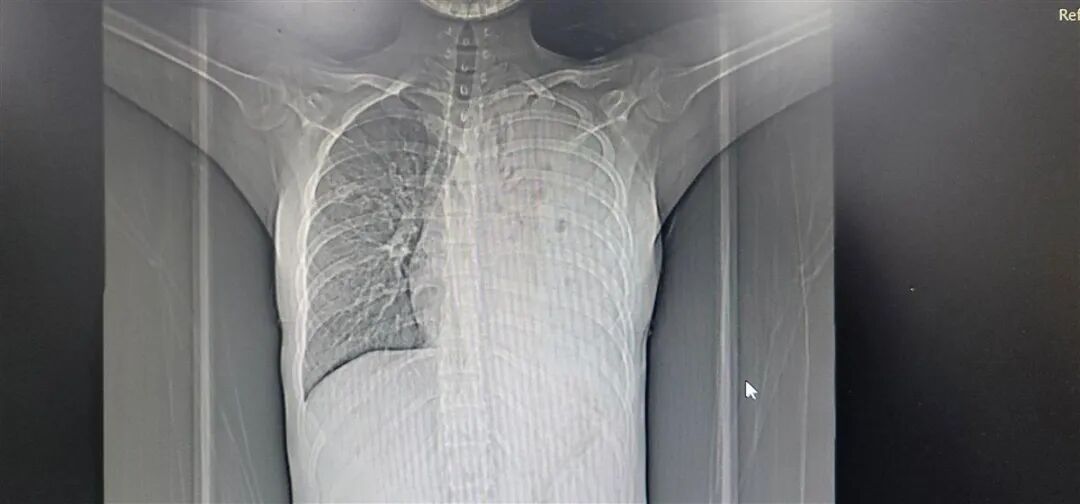

3个月后,小丽才被父母带到医院检查。医生看到CT片后,吃惊不已:左肺已经“不见了”。

CT影像中,左肺已经消失(右侧是左肺,CT影像是镜像)/图源:极目新闻

医生根据各项检查结果,综合判断,小丽感染了结核病。再一查,她的父母也感染了结核病,好在情况没有小丽严重。

治疗了3个月,医生发现,小丽的左肺依旧没有出现在CT影像中,最终确认,小丽的左肺靠药物治疗已经无法恢复了,要消灭结核菌,治愈疾病,需要对左肺也就是“菌巢”进行手术处理。

经过5个多小时的手术,医生才艰难地将石头一样的左肺从胸腔壁上剔下,并厘清、剪除了它与主气管、血管之间的纠缠,最终清理出胸腔。小丽也成为在该院接受全肺切除的最小患者。

医生介绍,结核菌侵蚀左肺后,产生炎症粘连,让左肺支气管逐渐狭窄、闭塞,造成气体无法交换,痰液无法排除,导致病情快速发展。此时,又加上小丽拖着没有规范治疗,让病菌进一步繁殖,病情进一步恶化,最终让左肺实变,并从CT影像中消失。这一病例,实在令人扼腕叹息。